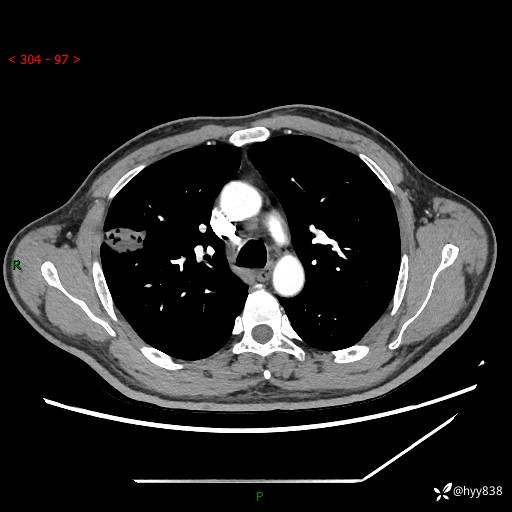

现病史:患者2天前体检完善胸部CT提示:右上肺团块影,炎症可能,肿瘤性病变不除外,冠状动脉钙化,无咳嗽、咳痰,无寒战发热,无恶心、呕吐等其他特殊不适,未予以特殊治疗,现为明确病变性质来我院就诊,门诊以“肺肿物性质待查”收入我科。 起病以来,患者精神、饮食、睡眠可,大小便正常,体力体重较前无明显变化。

胸部CT平扫+增强